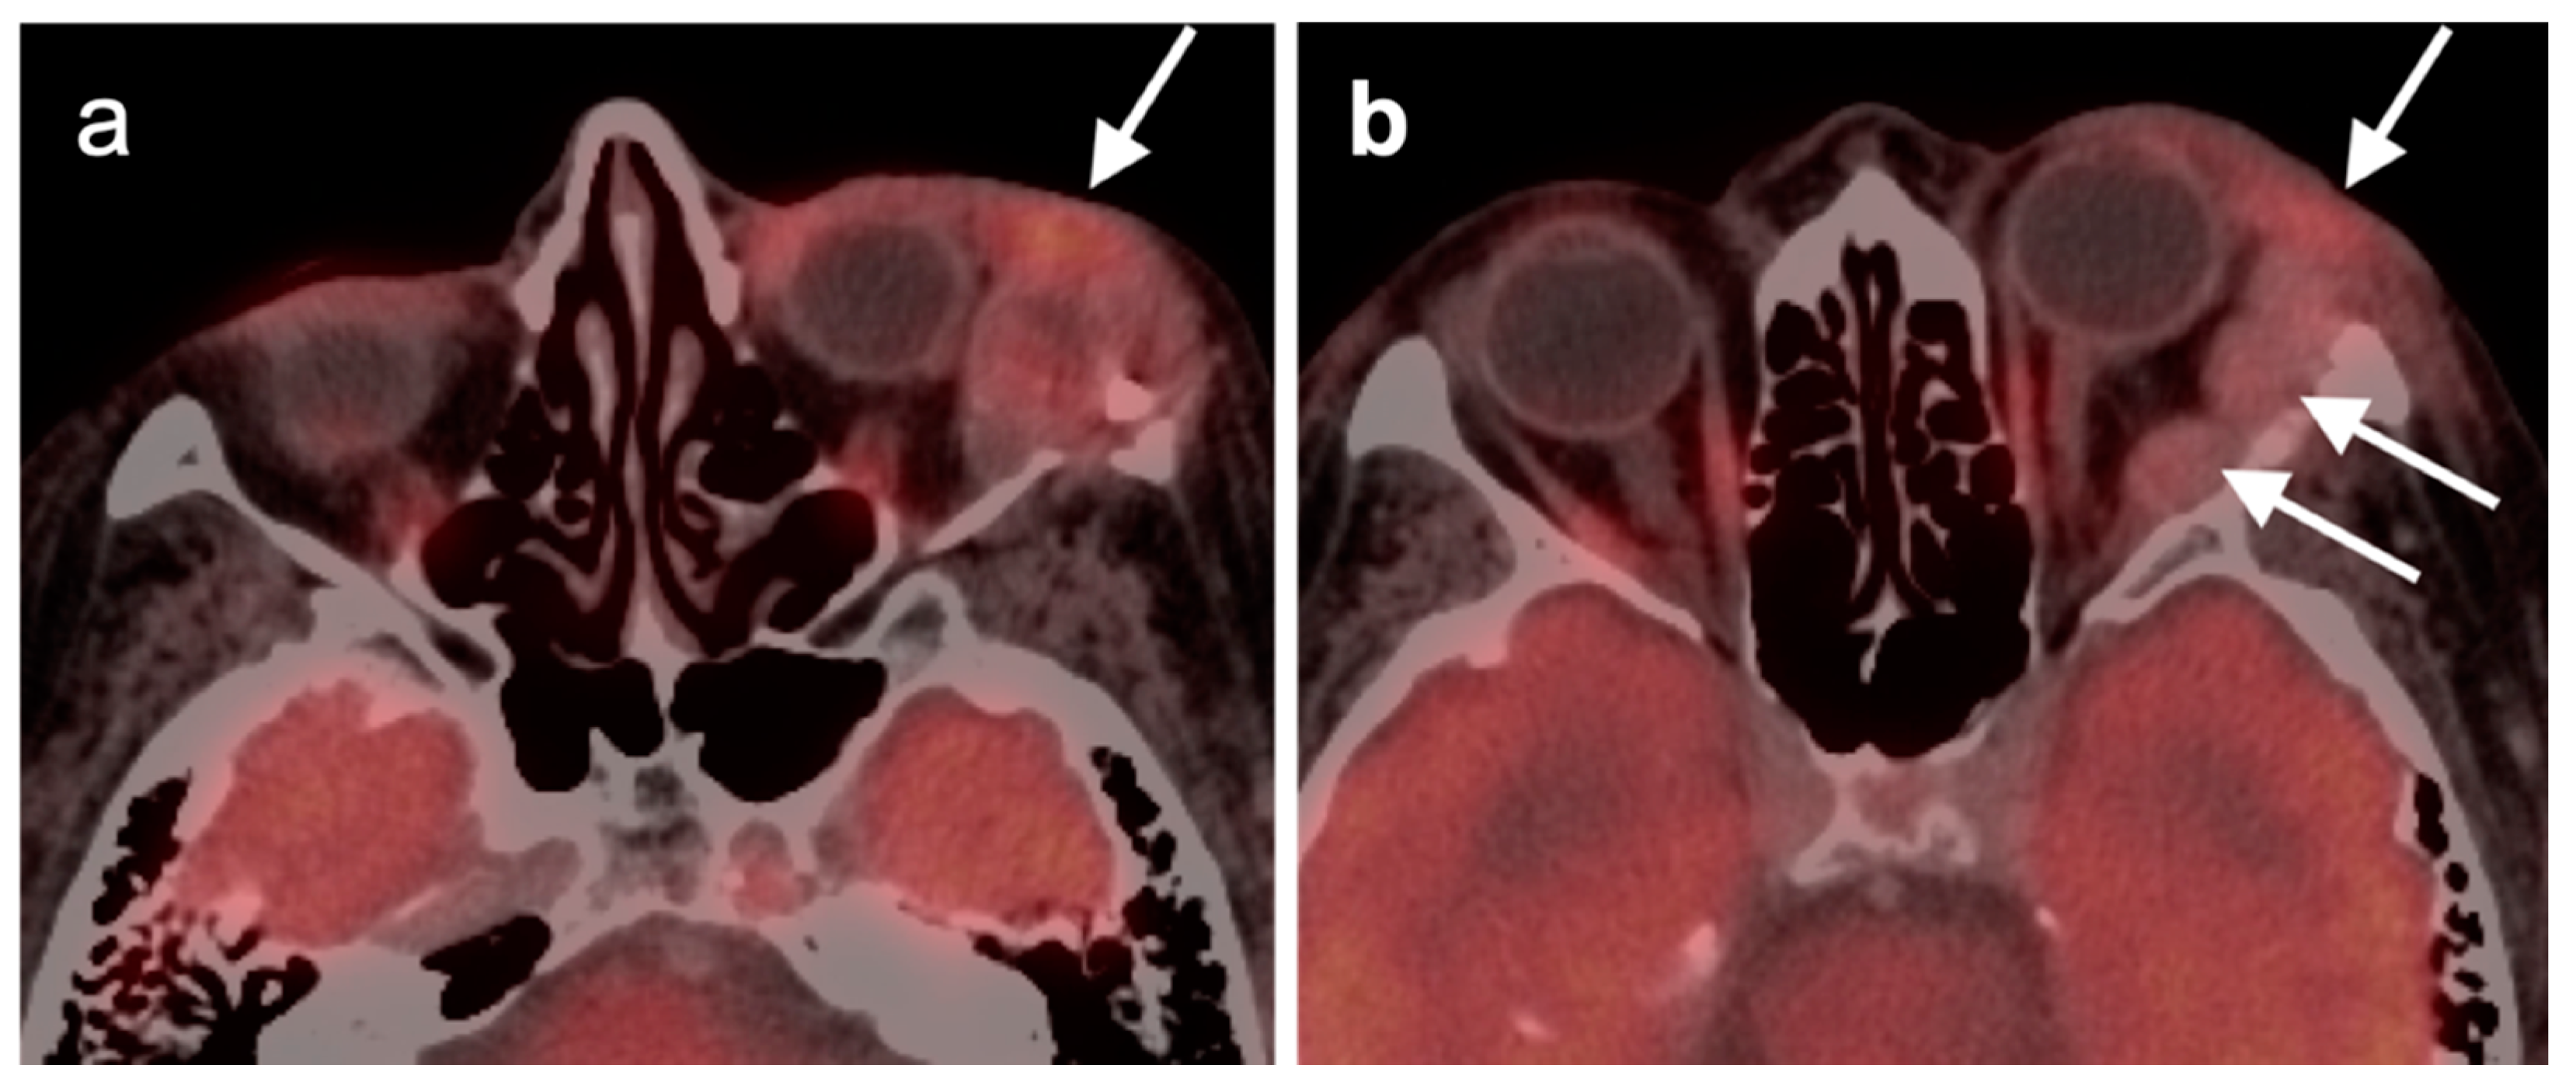

2.5. Major and Minor Salivary Gland, Lacrimal Gland Tumors

- Larson, C.R.; Wiggins, R.H. FDG-PET Imaging of Salivary Gland Tumors. Semin. Ultrasound CT MRI 2019, 40, 391–399. [Google Scholar] [CrossRef] [PubMed]

- Harrison, W.; Pittman, P.; Cummings, T. Pleomorphic adenoma of the lacrimal gland: A review with updates on malignant transformation and molecular genetics. Saudi J. Ophthalmol. 2018, 32, 13–16. [Google Scholar] [CrossRef]

- Avdagic, E.; Farber, N.; Katabi, N.; Shinder, R. Carcinoma Ex Pleomorphic Adenoma of the Lacrimal Gland with Epithelial-Myoepithelial Carcinoma Histologic Type. Ophthalmic Plast. Reconstr. Surg. 2017, 33, S136–S138. [Google Scholar] [CrossRef]